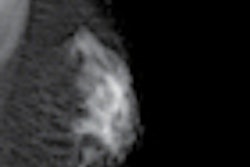

The firm said Roche is using Icon's Medical Image Review and Analysis (MIRA) software as a central repository for medical imaging.

MIRA software provides functionality for imaging and clinical data management, image analysis, project management, and document management. Imaging data can be accessed on a 24/7 basis by authorized users working anywhere in the world.